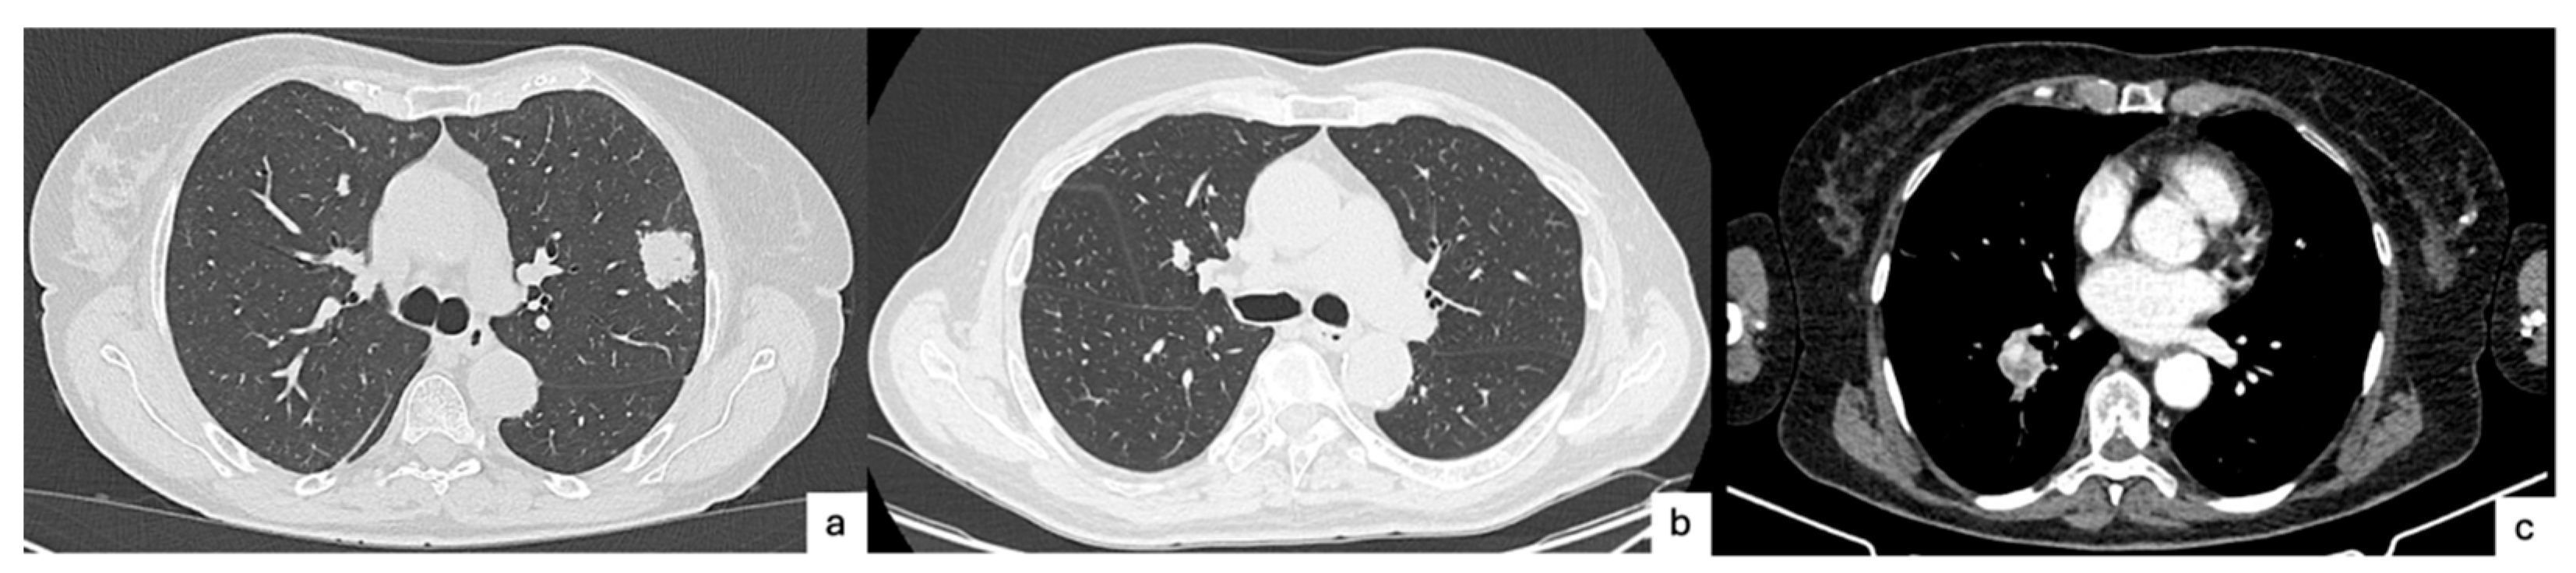

3. Radiologic Perspective